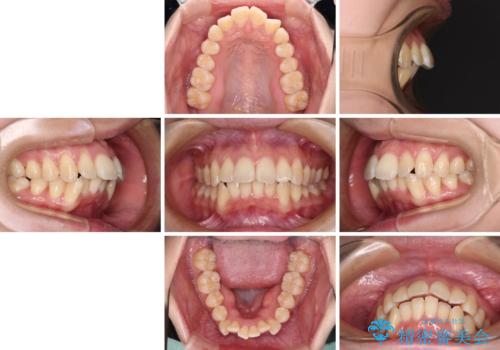

- 前歯の出っ歯と口元の閉じにくさを気にして来院された患者様です。

口元を積極的に引っ込めるために、上下左右の小臼歯4本を抜歯し、目立たないワイヤー装置にて矯正治療を行うこととしました。

上下前歯の歯軸の角度が大きく改善され、お口を閉じたときに顎先に認められた梅干し様の皺も改善されました。